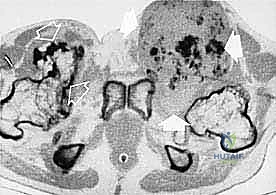

تحديد مراحل الورم (Staging): نظام Enneking

تحديد مرحلة الورم هو الخطوة الأهم قبل أي تدخل جراحي. يعتمد الدكتور هطيف على نظام (Enneking) لتحديد مراحل أورام العظام، والذي يعتمد على ثلاثة عوامل:

1. درجة الورم (Grade - G): بناءً على الفحص النسيجي (G1 منخفض الدرجة، G2 عالي الدرجة).

2. الموقع (Site - T): هل الورم داخل الحيز العظمي (Intracompartmental - T1) أم اخترق القشرة وخرج للحيز الخارجي (Extracompartmental - T2)؟

3. الانتشار (Metastasis - M): هل انتقل الورم لأعضاء أخرى (M0 لا يوجد، M1 يوجد انتشار)؟

بناءً على هذا التقييم الدقيق، يتم وضع خطة جراحية متكاملة لضمان استئصال الورم بالكامل دون ترك أي خلايا سرطانية.